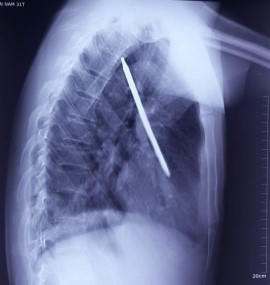

Nam bệnh nhân được đưa đến bệnh viện với 1 chiếc tuốc nơ vít dài 20 cm cắm sâu vào lồng ngực.